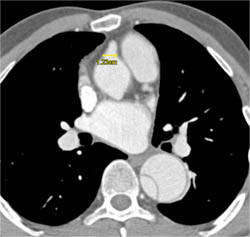

LAD Disease